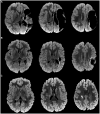

Unilateral spastic Cerebral Palsy (UCP) results from congenital brain injury, and Magnetic Resonance Imaging (MRI) has a role in understanding the etiology and severity of brain insult. In UCP, functional impairment predominantly occurs in the upper limb (UL) of the more affected side, where manual ability and dexterity are typically reduced. Also, mirror movements (MMs), are often present in UCP, with a further possible negative functional impact. This study aims to investigate the relationships among neuroanatomical characteristics of brain injury at MRI, manual functional impairment and MMs, in children with UCP. Thirty-five children with UCP participated in the study (20, M = 15, F, mean age 9.2 ± 3.5 years). Brain lesions at MRI were categorized according to the Magnetic Resonance Classification System (MRICS) and by using a semi-quantitative MRI (sqMRI) scale. Gross manual performance was assessed through Manual Ability Classification System (MACS) and the Box and Block Test (BBT), and MMs by Woods and Teuber scale, for both hands. Non-parametric correlation analyses were run to determine the relationship between neuroanatomical and functional features. Regression models were run to explore the contribution of neuroanatomical features and MMs to UL function. Correlation analyses revealed moderate to strong associations between sqMRI scores contralateral to the more affected side and UL functional impairment on MACS and BBT, with more severe brain injuries significantly correlating with poorer function in the more affected hand. No association emerged between brain lesion severity scores and MMs. MRICS showed no association with MACS or BBT, while a significant correlation emerged between MRICS category and MMs in the more affected hand, with brain lesion category that are suggestive of presumed earlier injury being associated with more severe MMs. Finally, exploratory regression analyses showed that neuroanatomical characteristics of brain injury and MMs contributed to the variability of UL functional impairment. This study contributes to the understanding of the neuroanatomical and neurological correlates of some aspects of manual functional impairment in UCP by using a simple clinical brain MRI assessment.